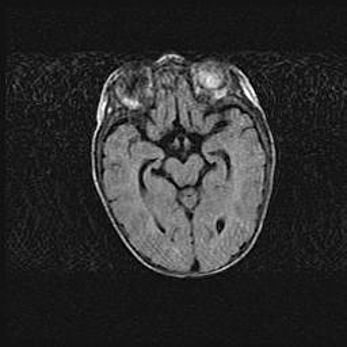

Открытая гидроцефалия.

Возраст: 9 месяцев 12 дней

Вес: 6800 г

Пол: мужской

Окружность головы: 41,5 см

Срок гестации: 28 недель

Гидроцефалия головного мозга у новорожденных имеет характерный признак: опережающий рост окружности головы приводит к визуально хорошо определяемой гидроцефальной форме сильно увеличенного в объёме черепа. Детские неврологи определяют следующие симптомы гидроцефалии у грудничков: выбухающий напряжённый родничок, частое запрокидывание головы, смещение глазных яблок к низу.